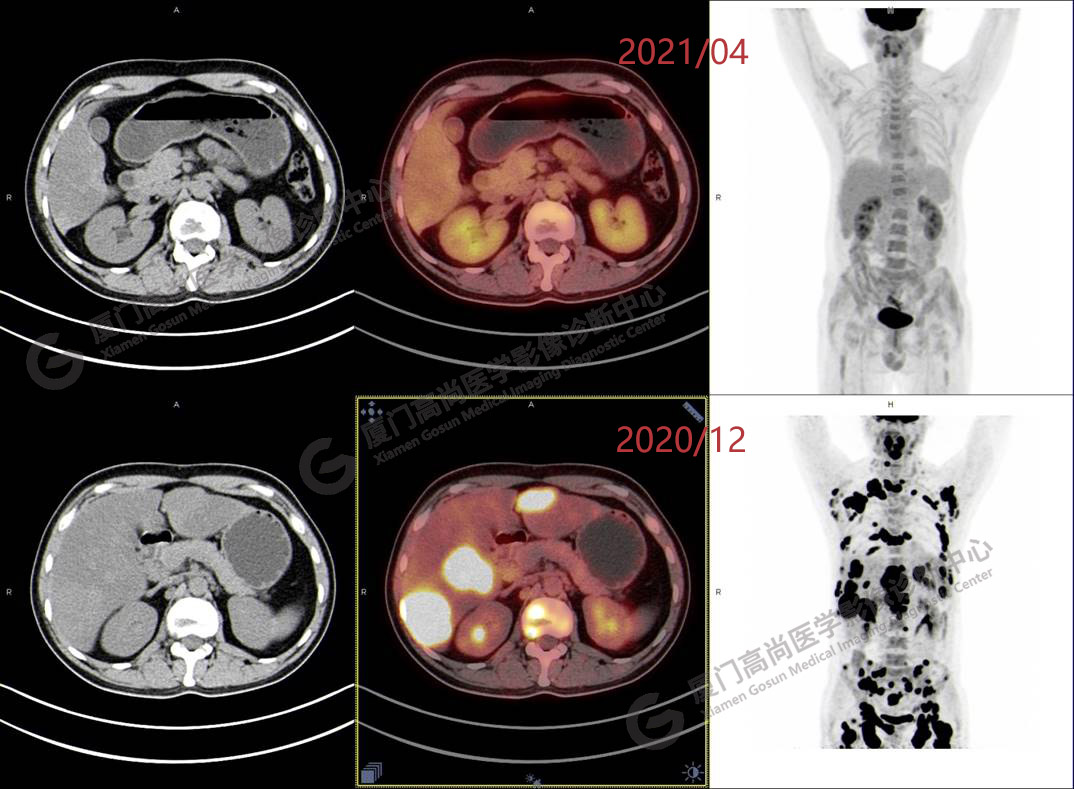

2020.12月本中心PET/CT示:全身多發(fā)腫大淋巴結(jié),代謝不同程度增高;肝臟多發(fā)稍高密度結(jié)節(jié)、脾臟多發(fā)稍低密度結(jié)節(jié),代謝異常增高;全身多發(fā)骨骼溶骨性骨質(zhì)破壞,代謝異常增高,胸2、腰1椎體病理性骨折,診斷為淋巴瘤。隨后,病理確診為彌漫大B細(xì)胞淋巴瘤。

患者化療4個(gè)療程后,于2021.04月返我中心復(fù)查,現(xiàn)患者本人已能自主行走,此次更是獨(dú)自一人來我中心復(fù)查PET/CT。檢查結(jié)果顯示:原全身多發(fā)病灶基本消失,且病灶代謝基本恢復(fù)正常。以下是患者PET/CT前后對(duì)比圖像:

圖片PET/CT前后對(duì)比圖像3